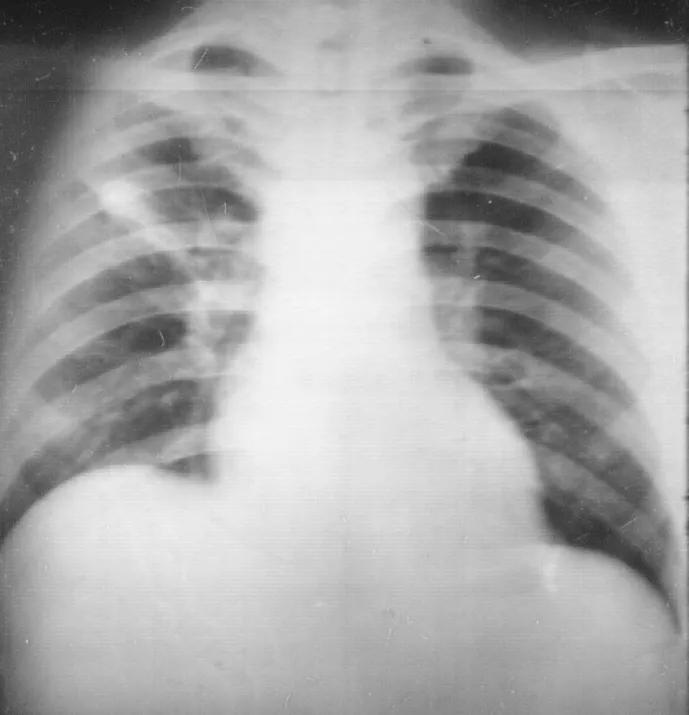

二、这是典型肺结核X线诊断特征:

目前的最新分类为:Ⅰ型: 原发综合征; Ⅱ型: 血行播散型; Ⅲ型: 继发性肺结核 (浸润性肺结核,空洞性肺结核,结核球,干酪样肺炎,纤维空洞型肺结核等); Ⅳ型: 结核性胸膜炎。

从影像学上,有可能表现为Ⅲ型继发性肺结核,也有可能更像原发综合征——有肺部淋巴结肿大、有肺内实质的浸润等等。

图:胸部CT:右侧液气胸,右肺实变,伴空洞及气液平。